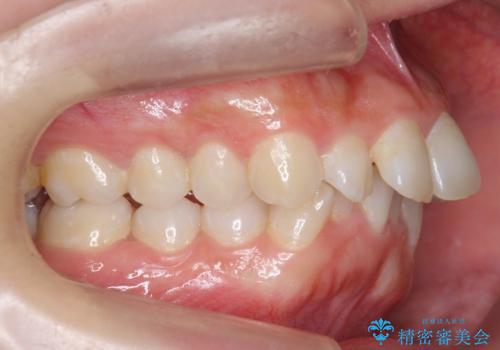

前歯をさげたい 歯を抜かずに マウスピース矯正で治したい

- 上の前歯が出ているとのことで来院。

歯を抜かずに、上の奥歯を後ろにさげつつ上の前歯を小さく少し削る処置を行い前歯の角度を修正しました。

右上下の奥歯もすれ違い咬合も、治療で改善しています。

下の前歯が生まれつき3本でしたので上下の正中は合わない仕上がりとなります。